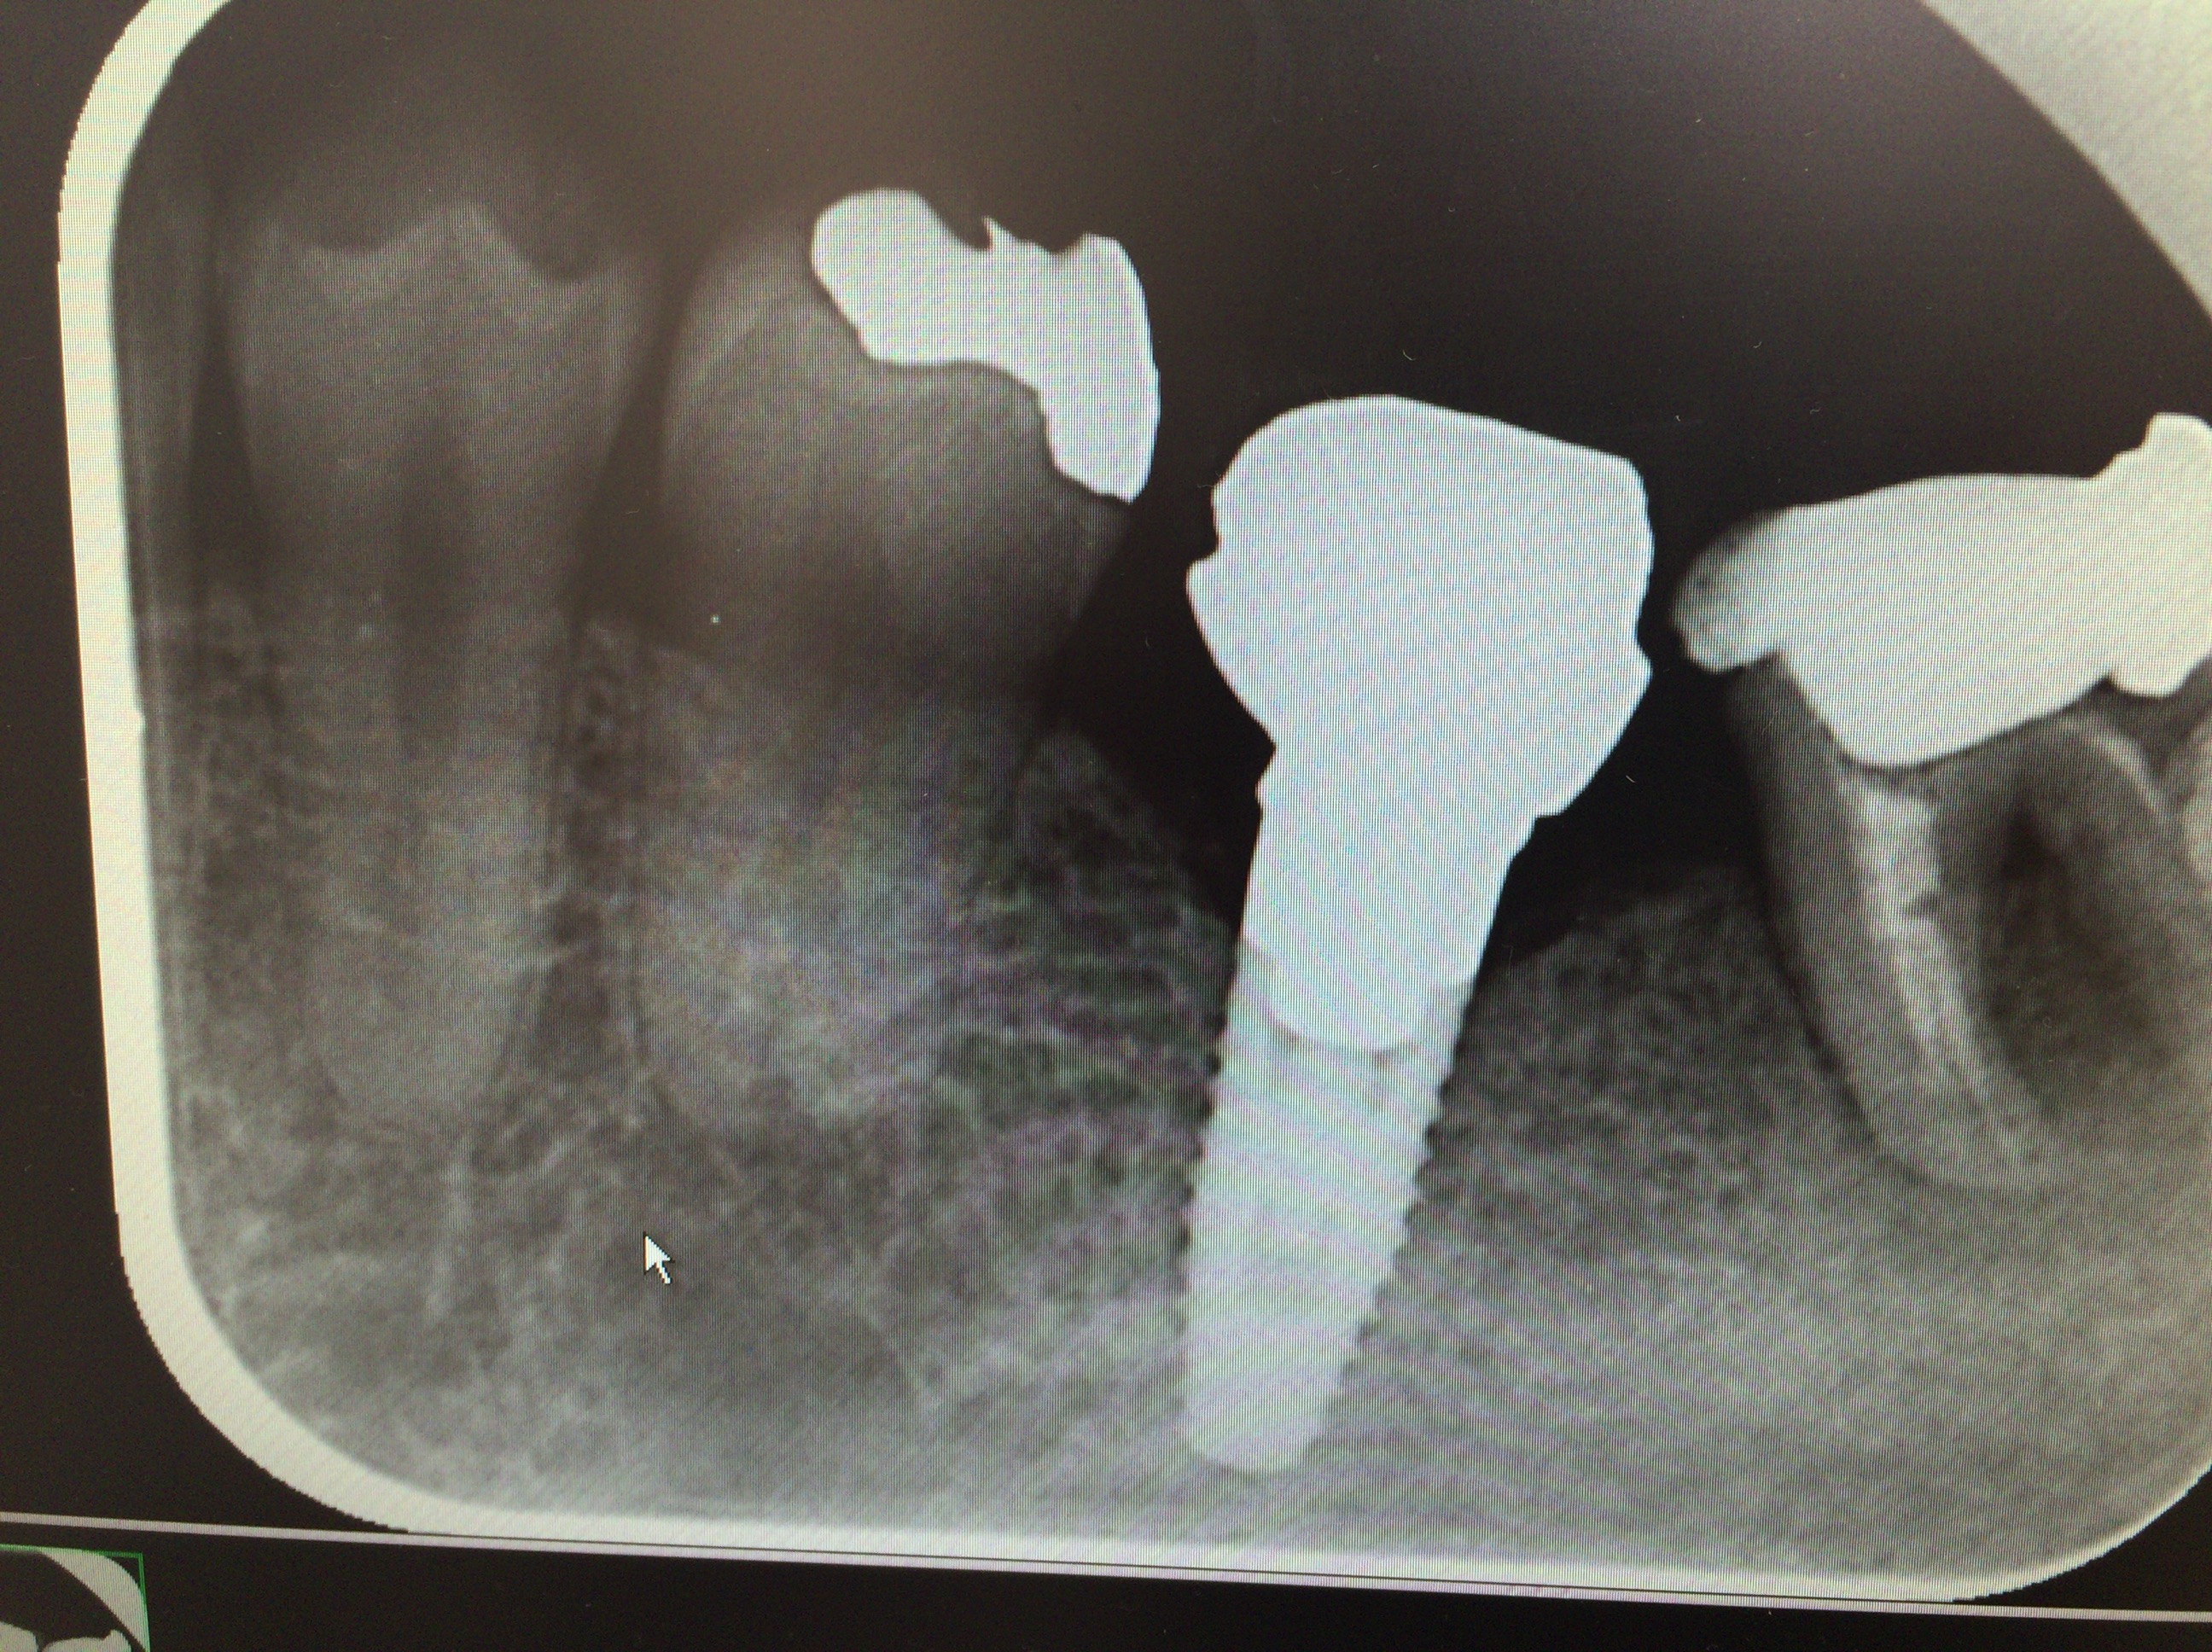

レントゲンをお見せします!

インプラントの下の部分のネジ様にガタガタしてい

る部分の周囲に少し分かりづらいですが、帯状の影

があります、(※矢印は関係ありません)

この様にネジ周りにうっすらと影ができるのは、

顎の骨にくっつかずに、炎症を起こして、骨が溶け

ている、証拠です!こうなると、もう駄目!

治りません、早々に撤去するしか、ありません。